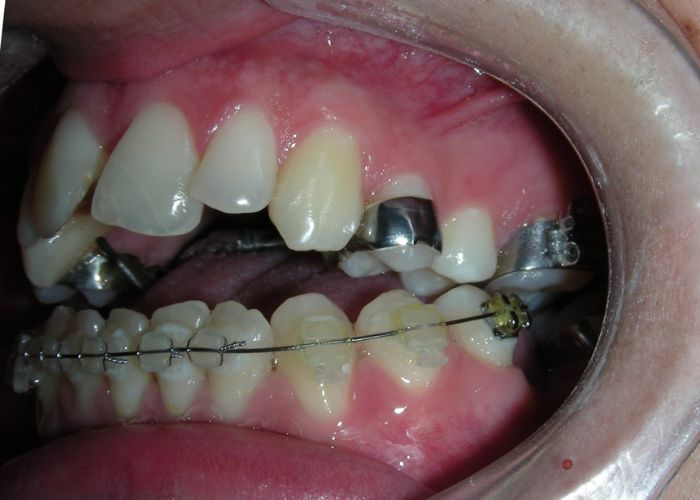

Was installed a Hyrax-type 10mm palatal expander of the Brazilian trademark Morelli® , modified by the author to be adapted to receive TADs microscrews, in order to initiate maxillary disjunction with MARPE (Mini-implant Assisted Rapid Palatal Expansion), TADS was installed with skeletal anchorage placed bilaterally having as references the roots of the maxillary canines and first premolars. Prior to insertion, local infiltrative anesthesia was administered using 2% lidocaine hydrochloride with 1:100,000 epinephrine. A total dose of approximately 0,8 mL per side (cortical infiltration technique). The TADs were inserted under aseptic conditions using a manual driver. Microscrew Evolution 1,6 Ø x 10 mm from the Argentine brand Odontit® . The Hyrax expander was then fitted and activated after 48 hrs .

Protocol of one activation per day was followed for a period of three weeks where the first clinical and radiographic evaluation was performed, showing clear signs of skeletal expansion, including the presence of a midline diastema. One more week of activations was added with a total of 28. The patient reported moderate headache during the first week of activation.

Having successfully achieved the expansion, we proceed to the intrusion of the posterior superior sectors, modifying the Hyrax by adding anchoring hooks at the buccal level of the first premolars. Using the Hyrax as anchorage, we sought a parallel intrusion. This could be replaced by a palatal bar. TADs were installed bilaterally at the mesial level of the first molars, inserting them as parallel as possible to the roots.

Simultaneously we begin with the alignment of the lower arch ,Simultaneously we began with the alignment of the lower arch with Roth prescription ceramic braces .022 . Henry Schein®